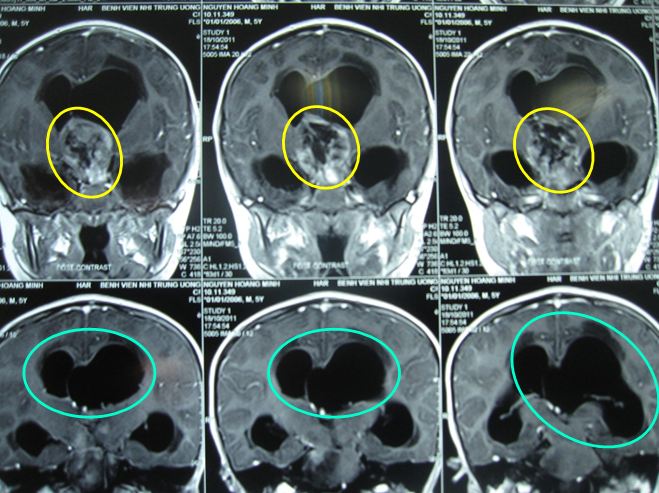

Sau xạ trị gia tốc với tổng liều 41,4Gy / 23 buổi, kết quả cho thấy:

• Kích thước khối u thu nhỏ lại rõ rệt: chỉ còn 1,5x1,8cm.

Sau xạ trị gia tốc đợt 2: Hình ảnh chụp cộng hưởng từ (MRI) sọ não:

Kích thước u thu nhỏ lại rõ rệt (trong vòng màu vàng)

Trước điều trị: Đau đầu, U kích thước lớn: 4x5cm

Sau xạ trị: Lâm sàng tốt lên nhiều, u bé lại rõ rệt: 1,5x1,8cm